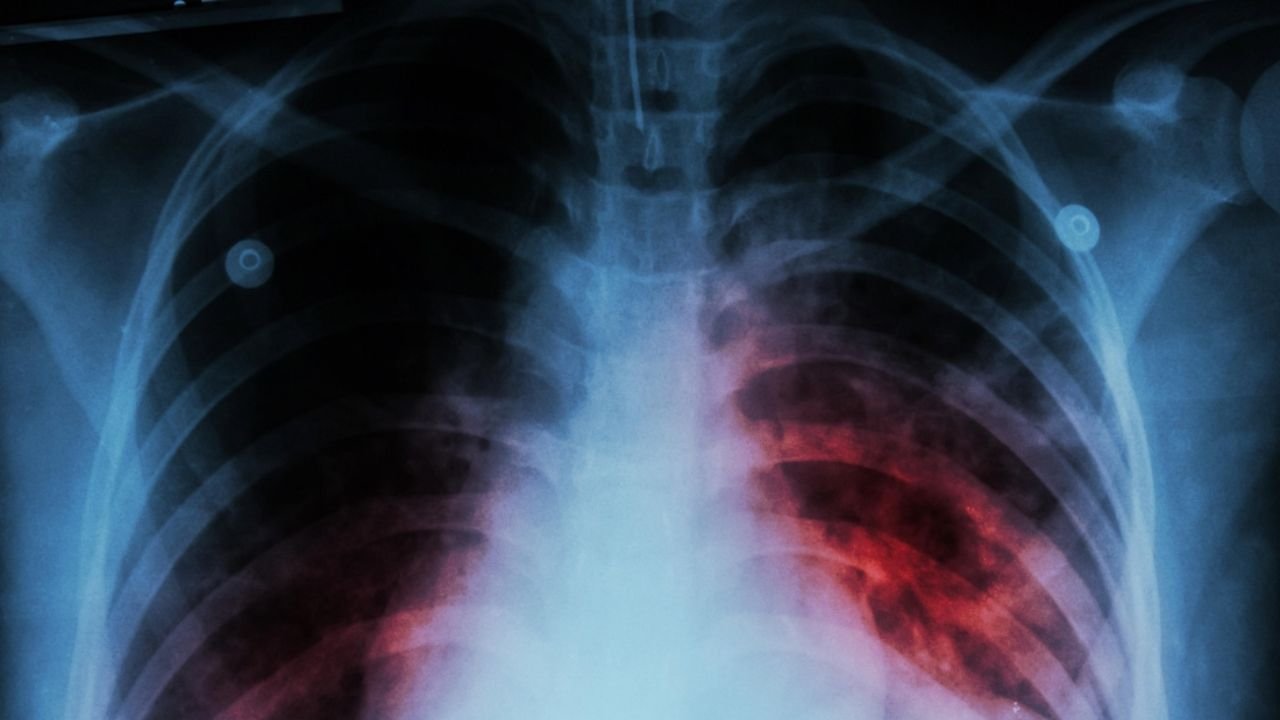

Según el informe anual de la OMS, 10.6 millones de personas enfermaron en 2021 de tuberculosis -causada por una bacteria que ataca principalmente a los pulmones-, un aumento de 4.5% en un año.

La prevalencia de la tuberculosis resistente a los medicamentos también aumentó – un 3% entre 2020 y 2021 – con 450,000 nuevos casos de tuberculosis resistente a la rifampicina en 2021.